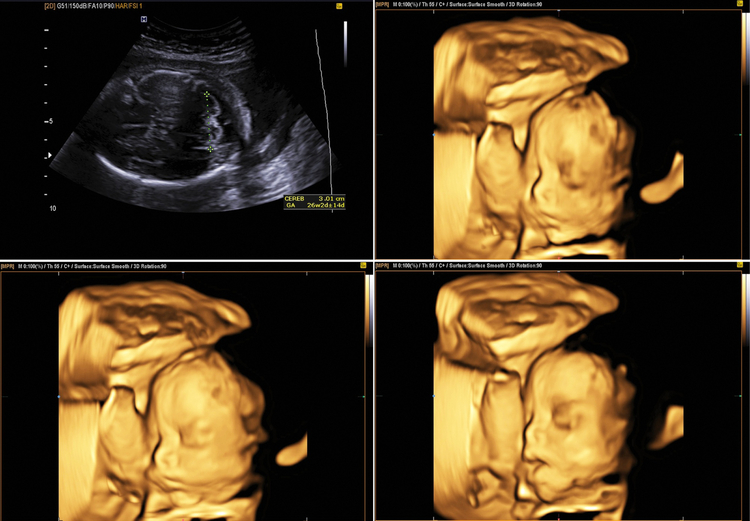

อัลตราซาวด์ 4 มิติ ช่วยให้คุณแม่เห็นใบหน้าและพัฒนาการของทารกในครรภ์ได้อย่างชัดเจน ตรวจหาความผิดปกติได้แม่นยำยิ่งขึ้น

เช็กพัฒนาการของทารก จากการตั้งครรภ์ด้วย Ultrasound 4D ตรวจความสมบูรณ์ 4 มิติ

แต่ความจริงแล้วในตอนนี้ ด้วยความที่เทคโนโลยีสุดแสนจะก้าวกระโดด ทำให้สามารถเห็นใบหน้าของลูกได้ชัดเจนมากขึ้น รวมถึงตรวจสอบพัฒนาการต่าง ๆ ผ่านการ Ultrasound 4D หรือในชื่อภาษาไทย “ตรวจความสมบูรณ์ 4 มิติ” ซึ่งนั่นหมายความว่าการอัลตราซาวด์ชนิดนี้ จะเห็นเด็กในระหว่างการตั้งครรภ์ ได้อย่างละเอียด

อัลตราซาวด์ 4 มิติ เป็นเครื่องมืออัลตราซาวด์ที่ละเอียดที่สุด โดยสิ่งที่เพิ่มจากความกว้าง ความยาว ความลึก คือ เวลา นำภาพแต่ละช่วงเวลามาประมวลผล และจัดเรียงรูปจนเกิดเป็นภาพเคลื่อนไหวที่เสมือนจริง ทำให้เห็นรายละเอียดของทารกชัดที่สุดในบรรดาอัลตราซาวด์ทุกแบบ

หลักการทำงานของ Ultrasound 4D มีอะไรบ้าง ขอขยายเพิ่มเติมจากด้านบน อัลตราซาวด์ 4D เป็นการนำเทคโนโลยีคลื่นเสียงความถี่สูงมาประยุกต์ใช้ในการสร้างภาพสามมิติของทารกในครรภ์ และเมื่อนำภาพสามมิติเหล่านี้มาเรียงต่อกันตามลำดับเวลา ก็จะได้ภาพเคลื่อนไหวที่แสดงให้เห็นพัฒนาการของทารกได้อย่างชัดเจน โดยสรุปหลักการทำงานได้ดังนี้

การทำ Ultrasound 4D ตรวจความสมบูรณ์ 4 มิติ เริ่มทำได้ตั้งแต่สัปดาห์ที่ 26-28 ของการตั้งครรภ์ แต่ไม่ควรเกินสัปดาห์ที่ 35 เพราะเวลานั้นเด็กอาจจะกำลังเริ่มกลับหัวสำหรับเตรียมพร้อมในการลืมตาออกมาดูโลกภายนอกแล้ว